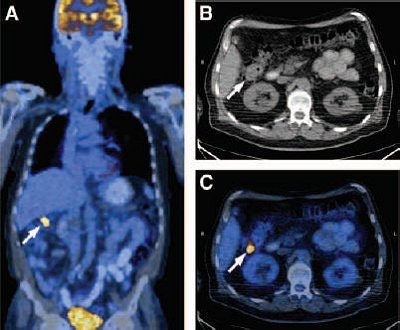

![]() |

| Coronal PET/CT (A), transaxial CT (B), and transaxial PET/CT (C) images from 69-year-old man show pathologic F-18 FDG accumulation with correlative soft-tissue density (arrows) in right colonic flexure. Endoscopic and histopathologic examinations revealed advanced colonic adenoma. Ehab M. Kamel, Miriam Thumshirn, Kaspar Truninger, Marc Schiesser, Michael Fried, Barbara Padberg, Didier Schneiter, Sandro J. Stoeckli, Gustav K. von Schulthess, and Katrin D.M. Stumpe. Significance of Incidental 18-F-FDG Accumulations in the Gastrointestinal Tract in PET/CT: Correlation with Endoscopic and Histopathologic Results. J Nucl Med 2004; 45;1804-1810, Figure 2. |